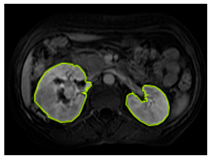

3.2.1. ROI Dataset

The images used in the study include different anatomical areas, such as the liver, spleen, and intestine. However, in order to process the data more quickly and provide more accurate results from the analysis, only the kidney areas (Regions of Interest, ROI) were extracted and evaluated. The Roboflow platform was used for spatial matching and segmentation of the kidneys. Polygonal ROI regions were defined by applying the semantic segmentation method, and then the transformations performed were verified by the radiologist, increasing the reliability of the system. In our study, MRI phase images were acquired at a resolution of 512 × 512 and the renal region of interest (ROI) was segmented and resized to 224 × 224 for input into the DenseNet architecture. In a similar study, Alhussaini et al. utilized 512 × 512 CT images and processed tumor-containing ROIs for their analysis; however, segmented region details were not provided [23]. Another study aimed to differentiate ccRCC from oncocytoma by extracting ROIs from T2-weighted images (T2-WI), pre-contrast T1-weighted images (T1-WI), and post-contrast arterial and venous phases. Tumor regions segmented at 100 × 100 mm were subsequently resized for input into the AlexNet model [24]. Unlike these studies, our approach involves segmenting the entire kidney, rather than solely the tumor region, to enable the deep learning model to leverage structural information for the organ as a whole.

Table 2 shows sample images containing ROI areas for different phases.

Table 2.

ROI areas in different phases.